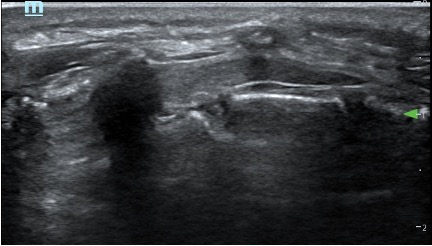

Caudal in a two year old